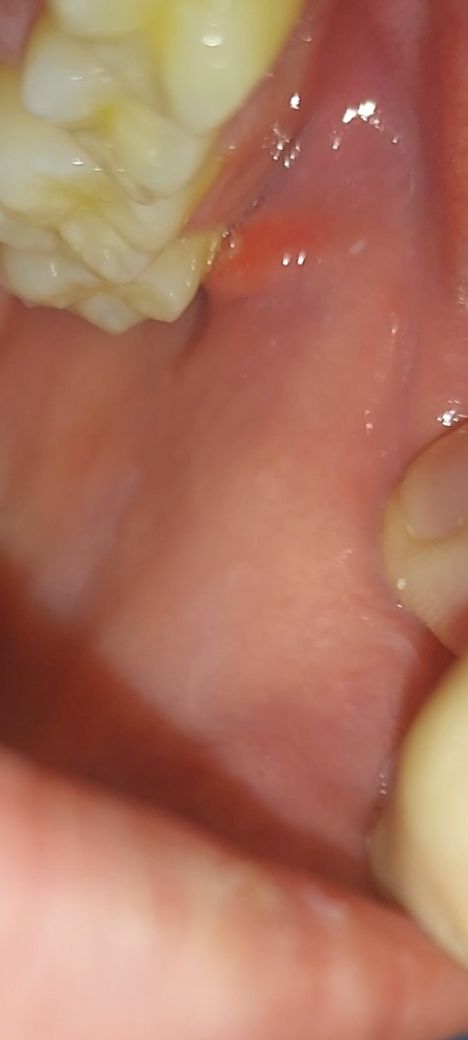

입 안에 난 물집?같은거 병원 가봐야될까요

입 안 볼에 이런 빨간색 물집같은게 생겼네요..병원 가봐야될까요? 한 3일됐습니다 너무 불안하네요.. 도와주세요!! 계속 신경쓰이네요.. 구강암은 아니겠죠..?? 병원가봐야되는지 알려주세요

• 1번 째 사진

볼쪽에 생긴 것이 3일 정도 되었다면 볼살이 씹혀서 생긴 것일 가능성이 많습니다.

대략 1주일 정도 지나면 저절로 없어질 것으로 보입니다.

빨간색형태의 물집이 있다면, 씹은 상처일수도 있고, 구내염의 가능성도 있습니다.

구강암일 가능성은 낮아보입니다. 구내염일 가능성이 높아 보이며 일시적으로 나타났을 수 있어 보입니다. 대부분 구내염은 2주 이내에 회복되고 특별한 치료를 요하지 않습니다. 물론 통증이 크다면 연고 등이나 마취 크림을 사용할 수 있습니다.

만약에 해당 병소가 2주 이상 지속된다면 이때는 치과 방문 후 정확한 감별진단을 받아보셔야 합니다.